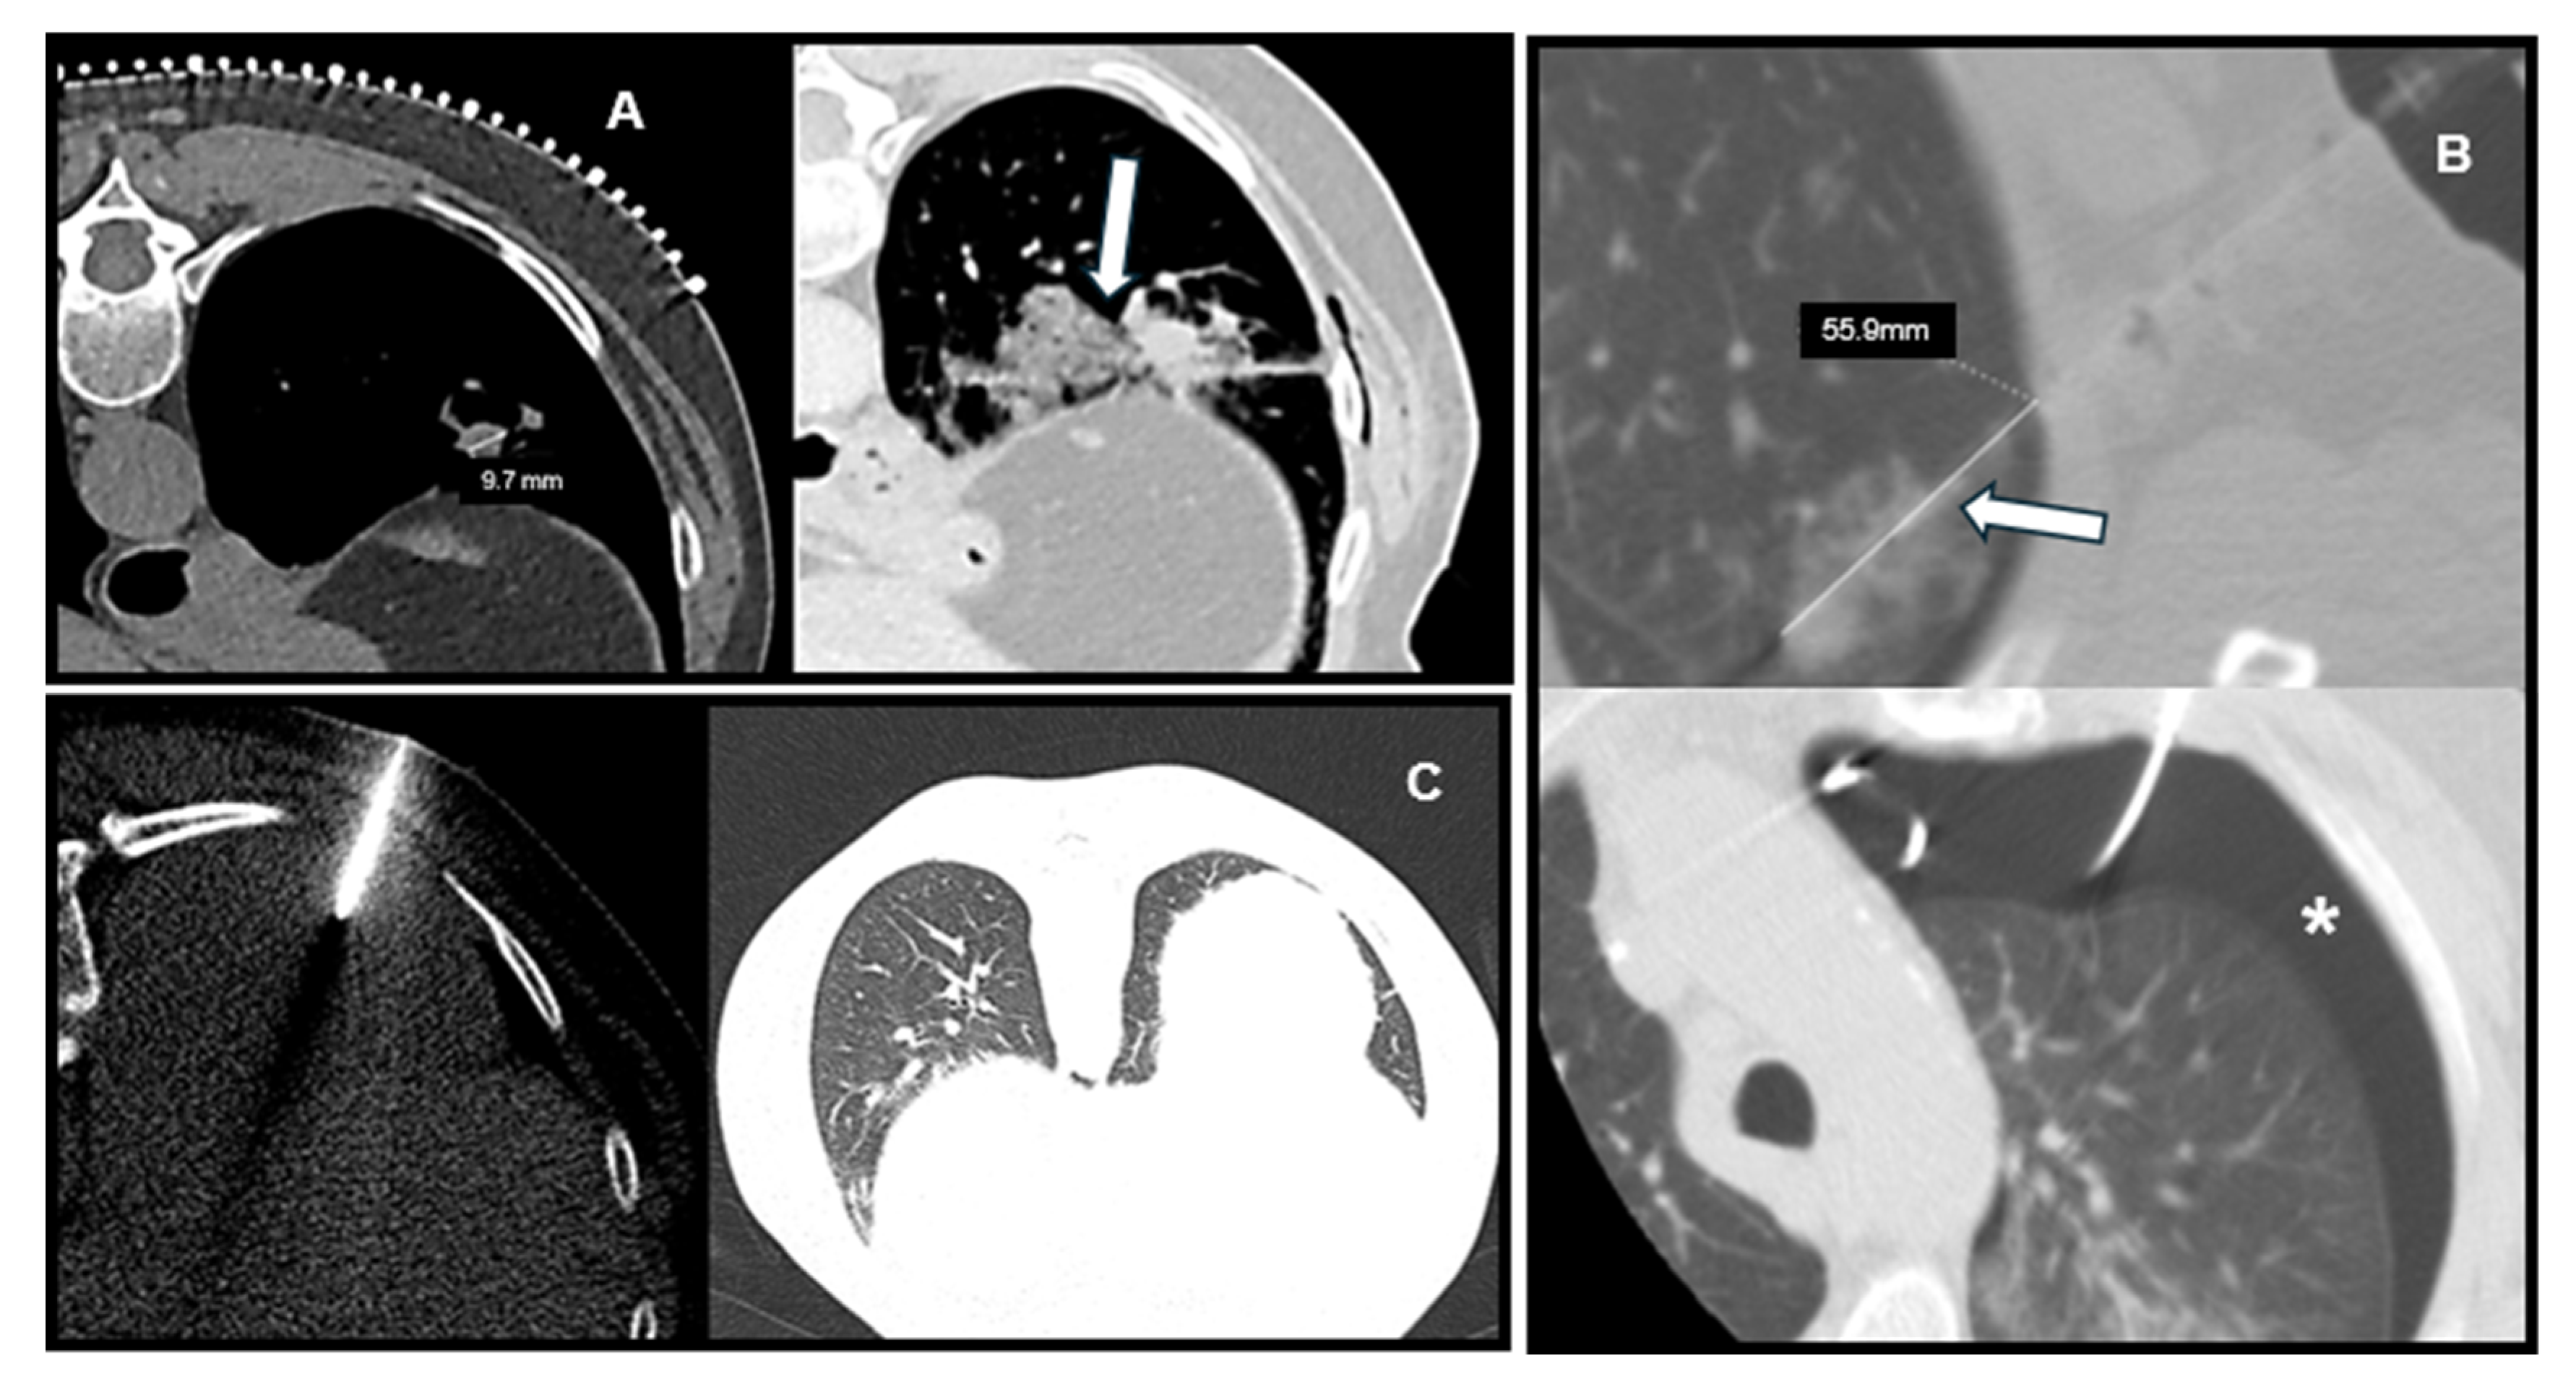

Representative CT images illustrating the relationship between lesion characteristics and post-biopsy complications are shown in Figure 3, including a deep lesion with PTX, a small lesion with hemorrhage, and a superficial lesion without complications.

Figure 3. Representative CT Images of Lesion Characteristics and Post-Biopsy Complications. (A) Small subpleural lesion (<30 mm) with focal parenchymal hemorrhage after biopsy (arrow). (B) Deep-seated lesion (>40 mm to pleura) with long intrapulmonary needle path (arrow) and resultant pneumothorax (star). (C) Superficial lesion with no pneumothorax or hemorrhage, illustrating low-risk profile.